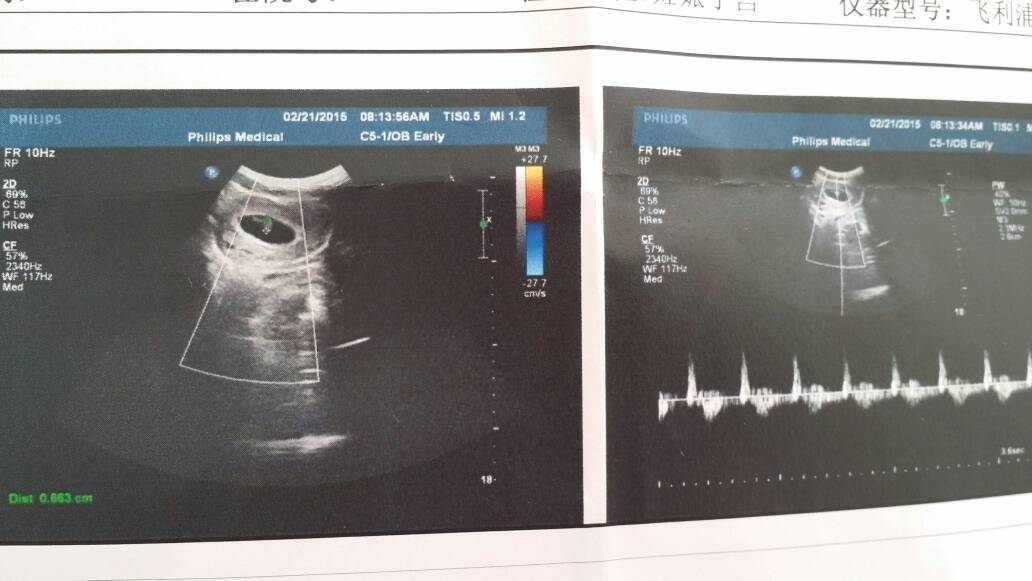

我想问问有懂这个彩超的吗?这个能看出男孩还是女孩吗? 我想问问有懂这个彩超的吗?这个能看出男孩还是女孩吗? 点击展开 喜洋洋150919 2015-03-03 10:53 为您推荐: 其他回答 男宝 😗😗😗😗😗 小淼妈咪 2015-03-03 15:41 单上是看不出来的 林晨妈咪! 2015-03-03 11:36 太小了 看不出来的 快乐莹莹的阿母 2015-03-03 11:18 哈哈,胎儿太小了,更本看不出来,消停等到五个月吧 z n 2015-03-03 11:11 我听老人说女孩b超是看不见脸是不是? 宝贝,爸爸妈妈都非常爱你 2015-03-03 11:06 加载更多 相关问题 彩超单子能看出男孩女孩吗? 怀孕44天做的彩超,显示约3 07* 91cm的任妊娠囊回声,请问能看出是男孩女孩来吗 怀孕四个月做的彩超,胎儿双顶径3 7股骨长2 1,,,怎么看出是男孩还是女孩